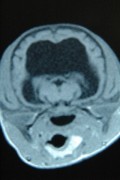

Hiernaast zie je enkele foto's van een operatie van een faraohondje met een waterhoofd.

De link vind je op : http://www.causus.be/draaiboek.cfm?Id=26&draaiboek_Id=108&Rubr=5